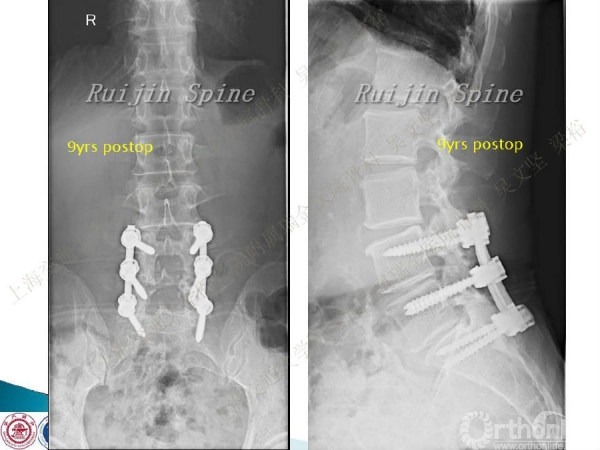

腰椎融合术后临近节段发生的退行性病变(adjacent segment disease,ASD))是一种常见的并发症。ASD的发病率相当高,而且涉及的范围很广。传统翻修手术治疗ASD有软组织剥离多、出血多、术后康复时间较长以及引起新的并发症的风险。本文结合病例介绍了运用Stand alone DLIF技术治疗ASD的方法与其优势。